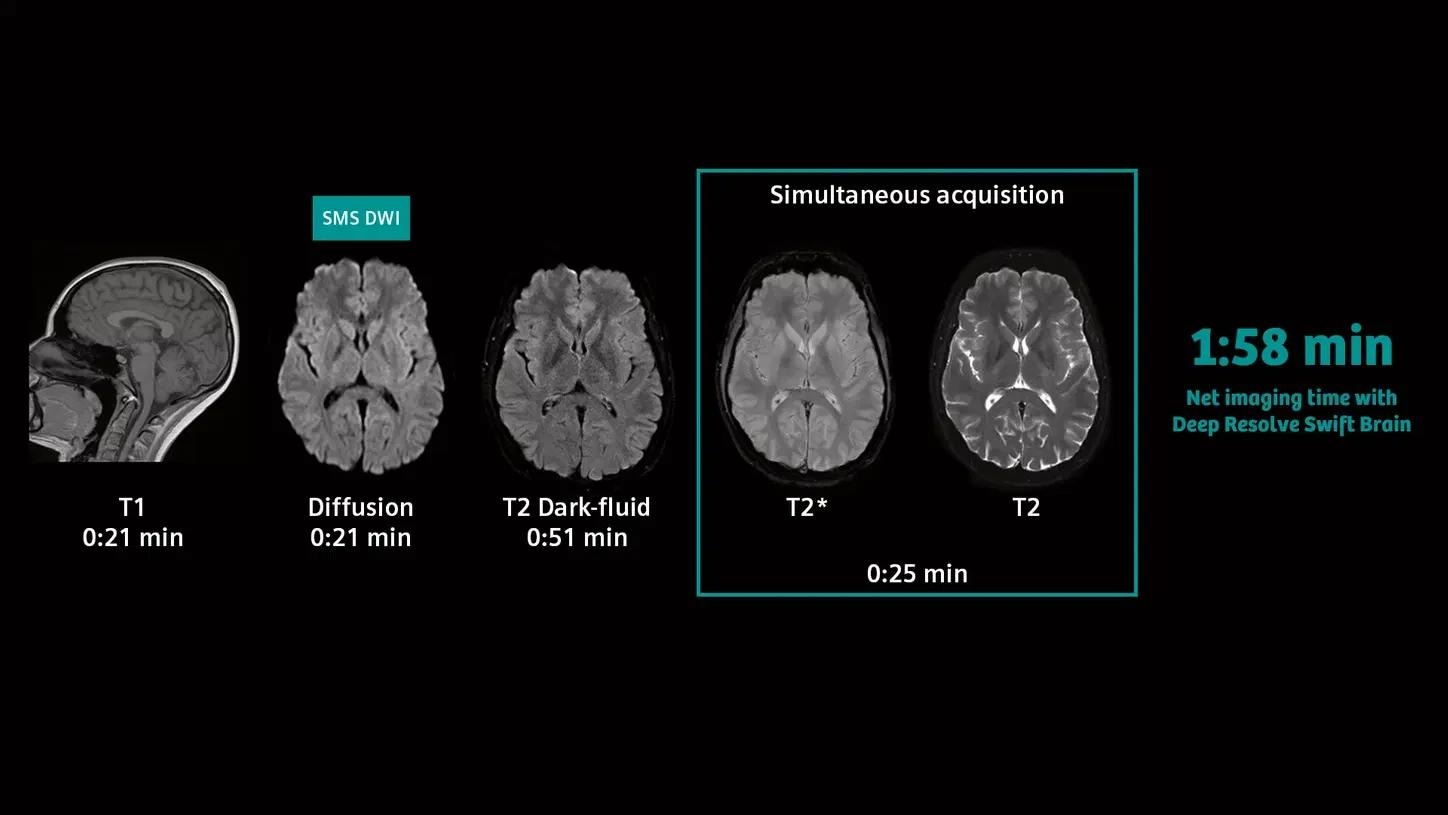

Deep Resolve—Faster than ever before

Deep Resolve is an AI-powered image reconstruction system that uses convolutional neural networks to expedite MR scans, making them faster than ever before. Faster scans increase workflow efficiency while boosting patient satisfaction.

Deep Resolve’s raw data-to-image reconstruction and extremely quick acquisition are game changers in MRI, allowing for the generation of actionable insights that can be diagnostically useful. In a secure digital environment, an open interface is intended to foster cooperation and co-creation. Deep Resolve technology is one step closer to creating a healthy world for all.

Neurology

Neurology

SMS RESOLVE

Exceptional diagnostic performance with RESOLVE using high-resolution DWI and DTI of the brain, as well as increased efficiency with Simultaneous Multi-Slice (SMS).

SMS RESOLVE

PAT 2 SMS 2, b1000| 1.0 × 1.0 × 4.0 mm3 | TA 2:32 minutes